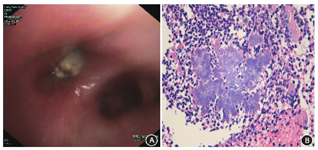

共25例(83.3%)行支气管镜检查,14例支气管镜检查异常者中5例表现为管腔内息肉样新生物,表面白色坏死物质(2例合并肺癌);9例表现为管腔黏膜炎性改变,黏膜肿胀、脓性分泌物或者血性分泌物,其中2例存在支气管异物(图2A),1例支气管内结石。25例行支气管镜检查者中,2例行经超声支气管镜肺活检。

注:A.支气管异物伴放线菌感染患者支气管镜检查下见右中叶开口异物阻塞,为骨性异物,黏膜充血肿胀;B.肺放线菌病患者肺组织炎性渗出物中大量中性粒细胞浸润,并见放线菌菌团(HE ×200)

所有病例均通过病理明确诊断。经支气管镜活检病理明确共9例(30.0%),其中2例经超声支气管镜肺活检病理明确,1例支气管镜下活检提示放线菌,但外科手术切除病理提示肺腺癌合并肉瘤样癌;2例(6.7%)经CT引导下经皮肺穿刺活检明确;1例(3.3%)经胸壁肿块穿刺病理明确;18例(60.0%)经外科手术切除病灶病理明确。病理学表现为:支气管黏膜及肺组织的慢性化脓性炎症,可见大量炎性细胞的浸润,伴有纤维组织增生和肉芽肿形成,局部脓性坏死物中可见真菌菌丝或菌团,形态上符合放线菌,显微镜下表现为菌落常呈菊花团状,中央紫蓝色,周围可见放射状排列的嗜伊红杵状体,末端呈棒状膨大(图2B)。本研究中12例(40.0%)行特殊染色,其中11例过碘酸雪夫(PAS)染色阳性,1例阴性;9例六胺银染色阳性,3例阴性;7例行抗酸染色阴性,5例未行抗酸染色。